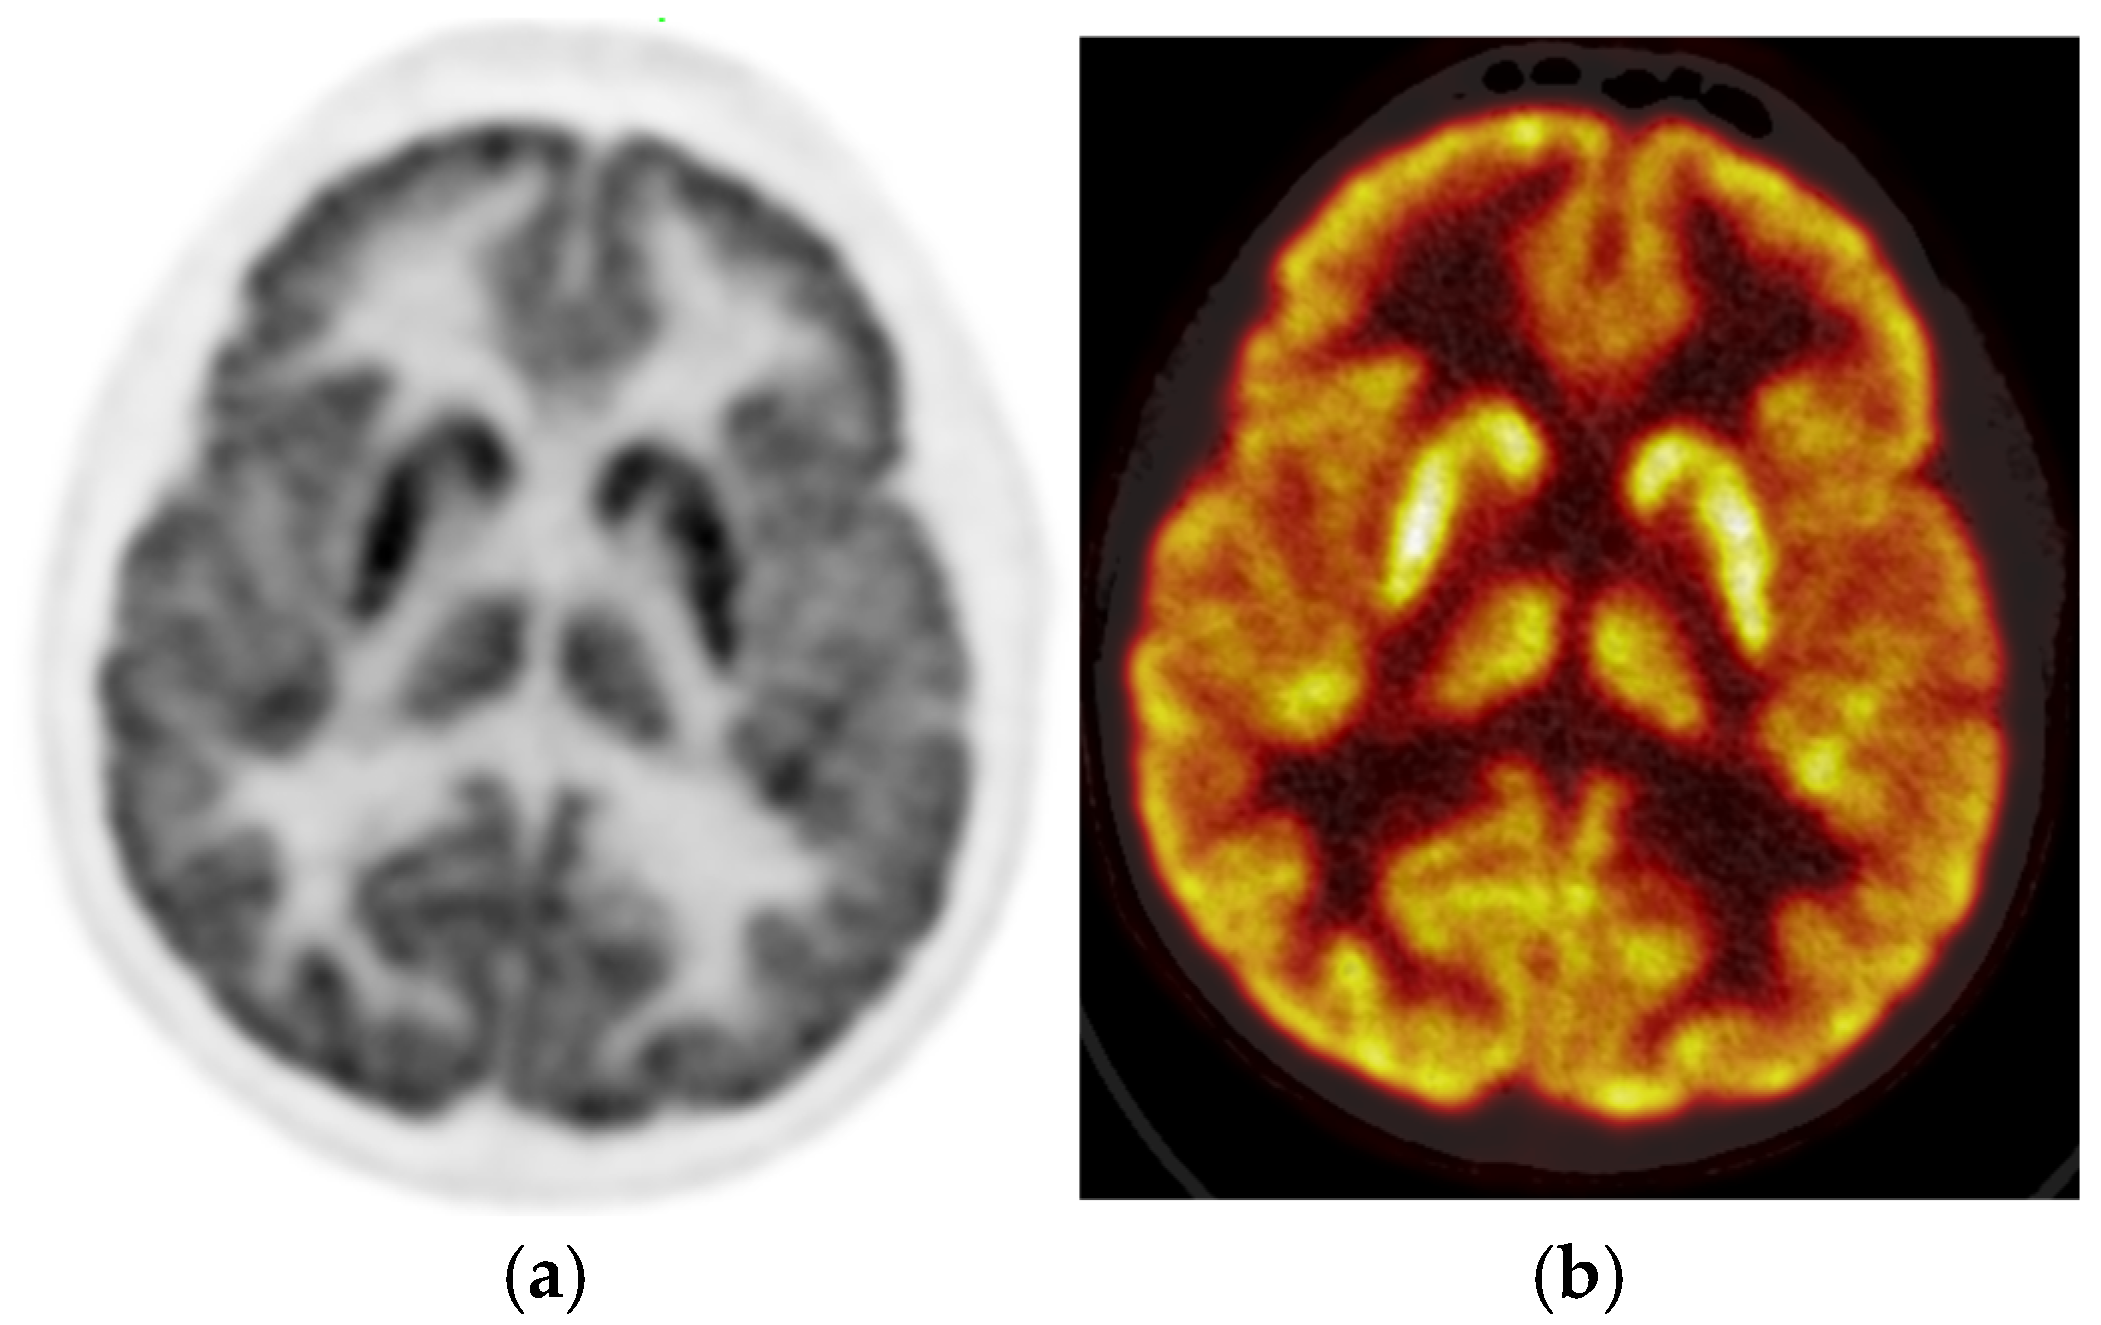

The PET images were reviewed and interpreted by two expert nuclear medicine physicians who were blinded; if there was any discrepancy, there was a consensus. Visual analysis was used to identify the location of the hypometabolic epileptogenic zone compared to the cortical activities. The metabolic activity of the bilateral thalamus was assessed qualitatively (thalamic 18F-FDG uptake in relation to the cerebral cortex and contralateral thalamus). Normal thalami are symmetric with metabolic activity similar to the normal cortex (Figure 2). Figure 3 demonstrates asymmetric decreased activity in the left temporal lobe as well as reduced left thalamus uptake.

Figure 2. Brain 18F-FDG PET, (a) (sagittal grey scale) and (b) (sagittal rainbow color) in a 16-year-old male with no definite cortical abnormality. The uptake of the thalami is also symmetric.